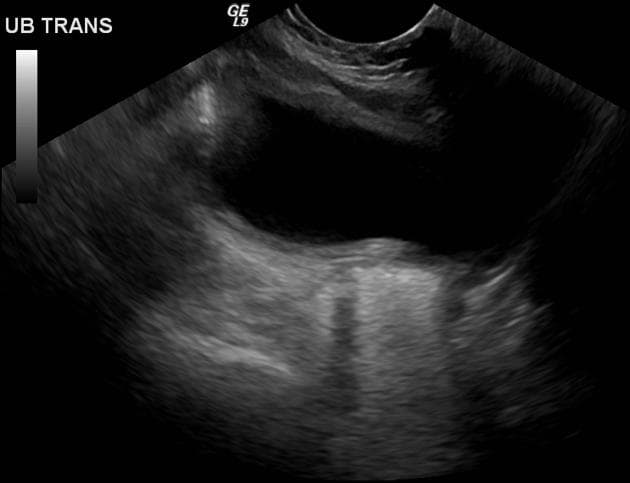

- Khối dạng nang (cystic mass) nằm ở vùng ngoại vi tuyến tiền liệt (peripheral prostate gland), phần trung tâm (center portion), có vẻ như không thông với niệu đạo tiền liệt tuyến (non communicating with the prostatic urethra).

Nang trong tuyến tiền liệt (intraprostatic cyst): có khả năng là nang ống Mullerian (probable Mullerian duct cyst).

Nang ống Mullerian là di tích bẩm sinh của ống Mullerian không thoái triển ở nam giới. Những nang này thường nằm ở đường giữa, phía sau niệu đạo tiền liệt tuyến và phía trên gò tinh (verumontanum). Một đặc điểm chẩn đoán quan trọng là chúng thường không thông với niệu đạo, giúp phân biệt với nang túi bầu dục tuyến tiền liệt. Về mặt lâm sàng, chúng có thể không có triệu chứng hoặc biểu hiện ở độ tuổi 30-40 với các triệu chứng như xuất tinh máu, đau vùng chậu hoặc tắc nghẽn đường tiểu. Trên chẩn đoán hình ảnh (siêu âm, CT hoặc MRI), chúng xuất hiện dưới dạng cấu trúc chứa dịch đơn thuần hoặc phức tạp mở rộng lên trên tuyến tiền liệt.